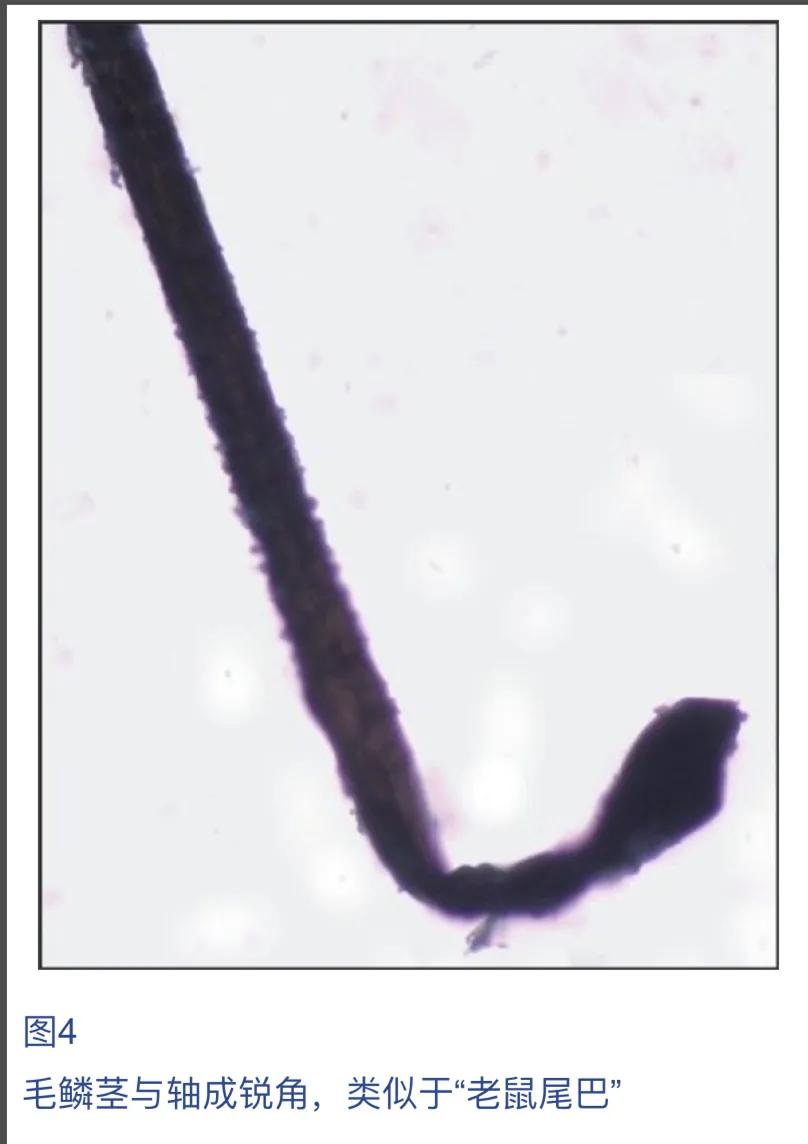

病因不明。可能与遗传或发育状况有关。是毛发内根鞘和毛囊表皮之间的粘附减弱。显微镜检查头发显示头发皱纹,有时呈皱巴巴袜子样或曲棍球棒样。

头发病理显示内、外毛根鞘裂隙。